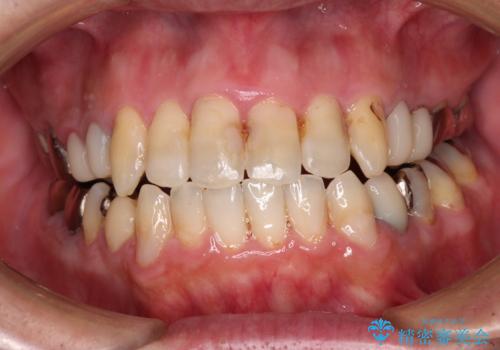

飛び出した前歯と目立つ銀歯 矯正とセラミックの総合歯科診療

- 飛び出している上顎前歯と、奥歯に多くある銀歯を気にして来院された患者様です。

マウスピースで矯正を行いたい反面、一旦早めに前歯を整えたいというご希望があったため、まずは上顎前歯をワイヤー装置で整え、その後インビザラインにて仕上げていくこととしました。

矯正治療後には、奥歯の銀歯をすべてセラミックにて補綴治療することとしました。

ワイヤー矯正を併用したことで、上顎前歯はあっという間に整いました。

補綴治療にあたり、痛みのある歯に対して根管治療を行うこととしましたが、処置が必要な歯が多かったため、期間を要しました。

補綴治療中に前歯のデコボコが戻ってしまったため、補綴治療後にインビザラインを1セット追加して仕上げました。